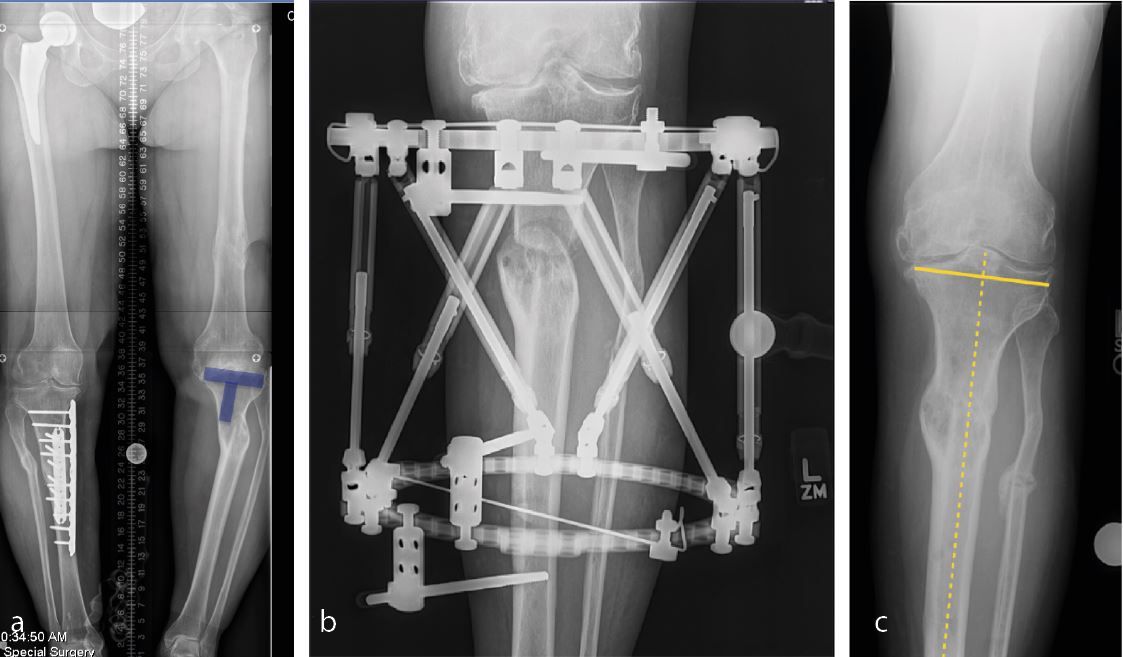

To make the decision, whether to correct the coronal deformity in a one stage or two stage fashion or to proceed with a primary total knee replacement the amount of angular deformity at the level of the knee provides the most reliable guidance. No matter where the extraarticular deformity is located doe the purpose of knee arthroplasty the overall mechanical deformity is measured as an angle between the mechanical axis of the femur (line through the center of the hip and the center of the distal femoral condyles) and the mechanical axis of the tibia (line through the center of the talus (ankle) and the center of the tibial plateau). A mechanical deformity in excess of 20-25 degrees usually suggests that a primary knee replacement without deformity correction is not possible. In these cases usually the deformity needs to be corrected first. For the correction of extraarticular deformities different options including correction over a nail, open osteotomy with plate fixation or external fixator exist. In my opinion the technique that interferes the least with the later total knee replacement should be favored. Open ostoeotomies and plate fixation should take into consideration the potential need for hardware removal at the time of surgery and plates should be placed medial along the standard medial parapatellar approach as often as possible. Correction using an intramedullary nail need to make sure that the nail does not extend into the bed of the primary knee implants and options for extramedullary alignment need to be available at the time of total knee arthroplasty (navigation, robotic or extramedullary alignment jigs) [3]. Finally, when using an external fixator, the risk of pin tract infection and osteomyelitis needs to be carefully weighed versus the ability for advanced 3-dimensional correction of the deformity. I personally had very good results with 2 stage correction using an external fixator or one stage correction using either an open plate fixation or intramedullary fixation using the stem of a revision femoral or tibial component. The later is especially appealing if the center of rotation and angulation (CORA) is close to the knee. Bony correction of the preexisting deformity renders the soft tissue balancing at the time of total knee replacement much easier and is usually indicated for less experienced surgeons. Rule of Thumb: For me a coronal deformity exceeding 25 degrees is an absolute and a deformity exceeding 20 degrees is a relative indication for a one stage or two stage correction of a preexisting extraarticular deformity (Figure 1a, b, c).

The usual back-up option of a hinge knee replacement does not exist in many of these patients since large extraarticular deformities away from the knee result in changes of the anatomical axis of the distal femur and proximal tibia and no longer allow for the use of a stemmed revision hinge implant. Occasionally in patients with a center of rotation and angulation (CORA) close to the knee one stage deformity correction can be done in the metaphyseal-diaphyseal junction using a intramedullary stem at the time of total knee arthroplasty. Care should be taken to secure rotational stability through implant press fit, alignment of the corrective osteotomy or an additional small plate.